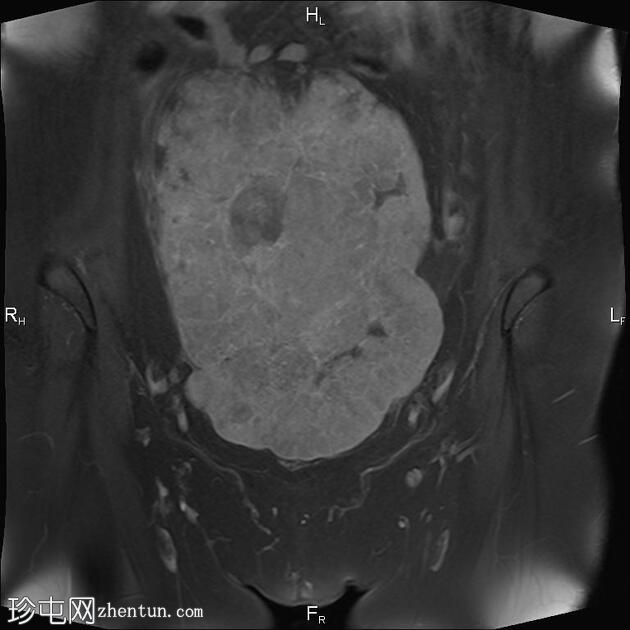

冠状位

T2

T1

盆腔内可见一巨大多分叶实性肿块,内部有隔膜,T2WI信号不均匀,T1WI信号不均匀,呈低信号。肿块内散在分布囊性/坏死性病变。

肿块外可见子宫和右侧卵巢,肿块似源自左侧卵巢。该肿块压迫膀胱和两侧远端输尿管,并导致肠管和血管结构移位,但无侵袭或包裹征象。

造影后,肿块呈不均匀强化,隔膜强化。

远端髂腹旁和两侧髂骨旁区域可见少量肿大淋巴结。